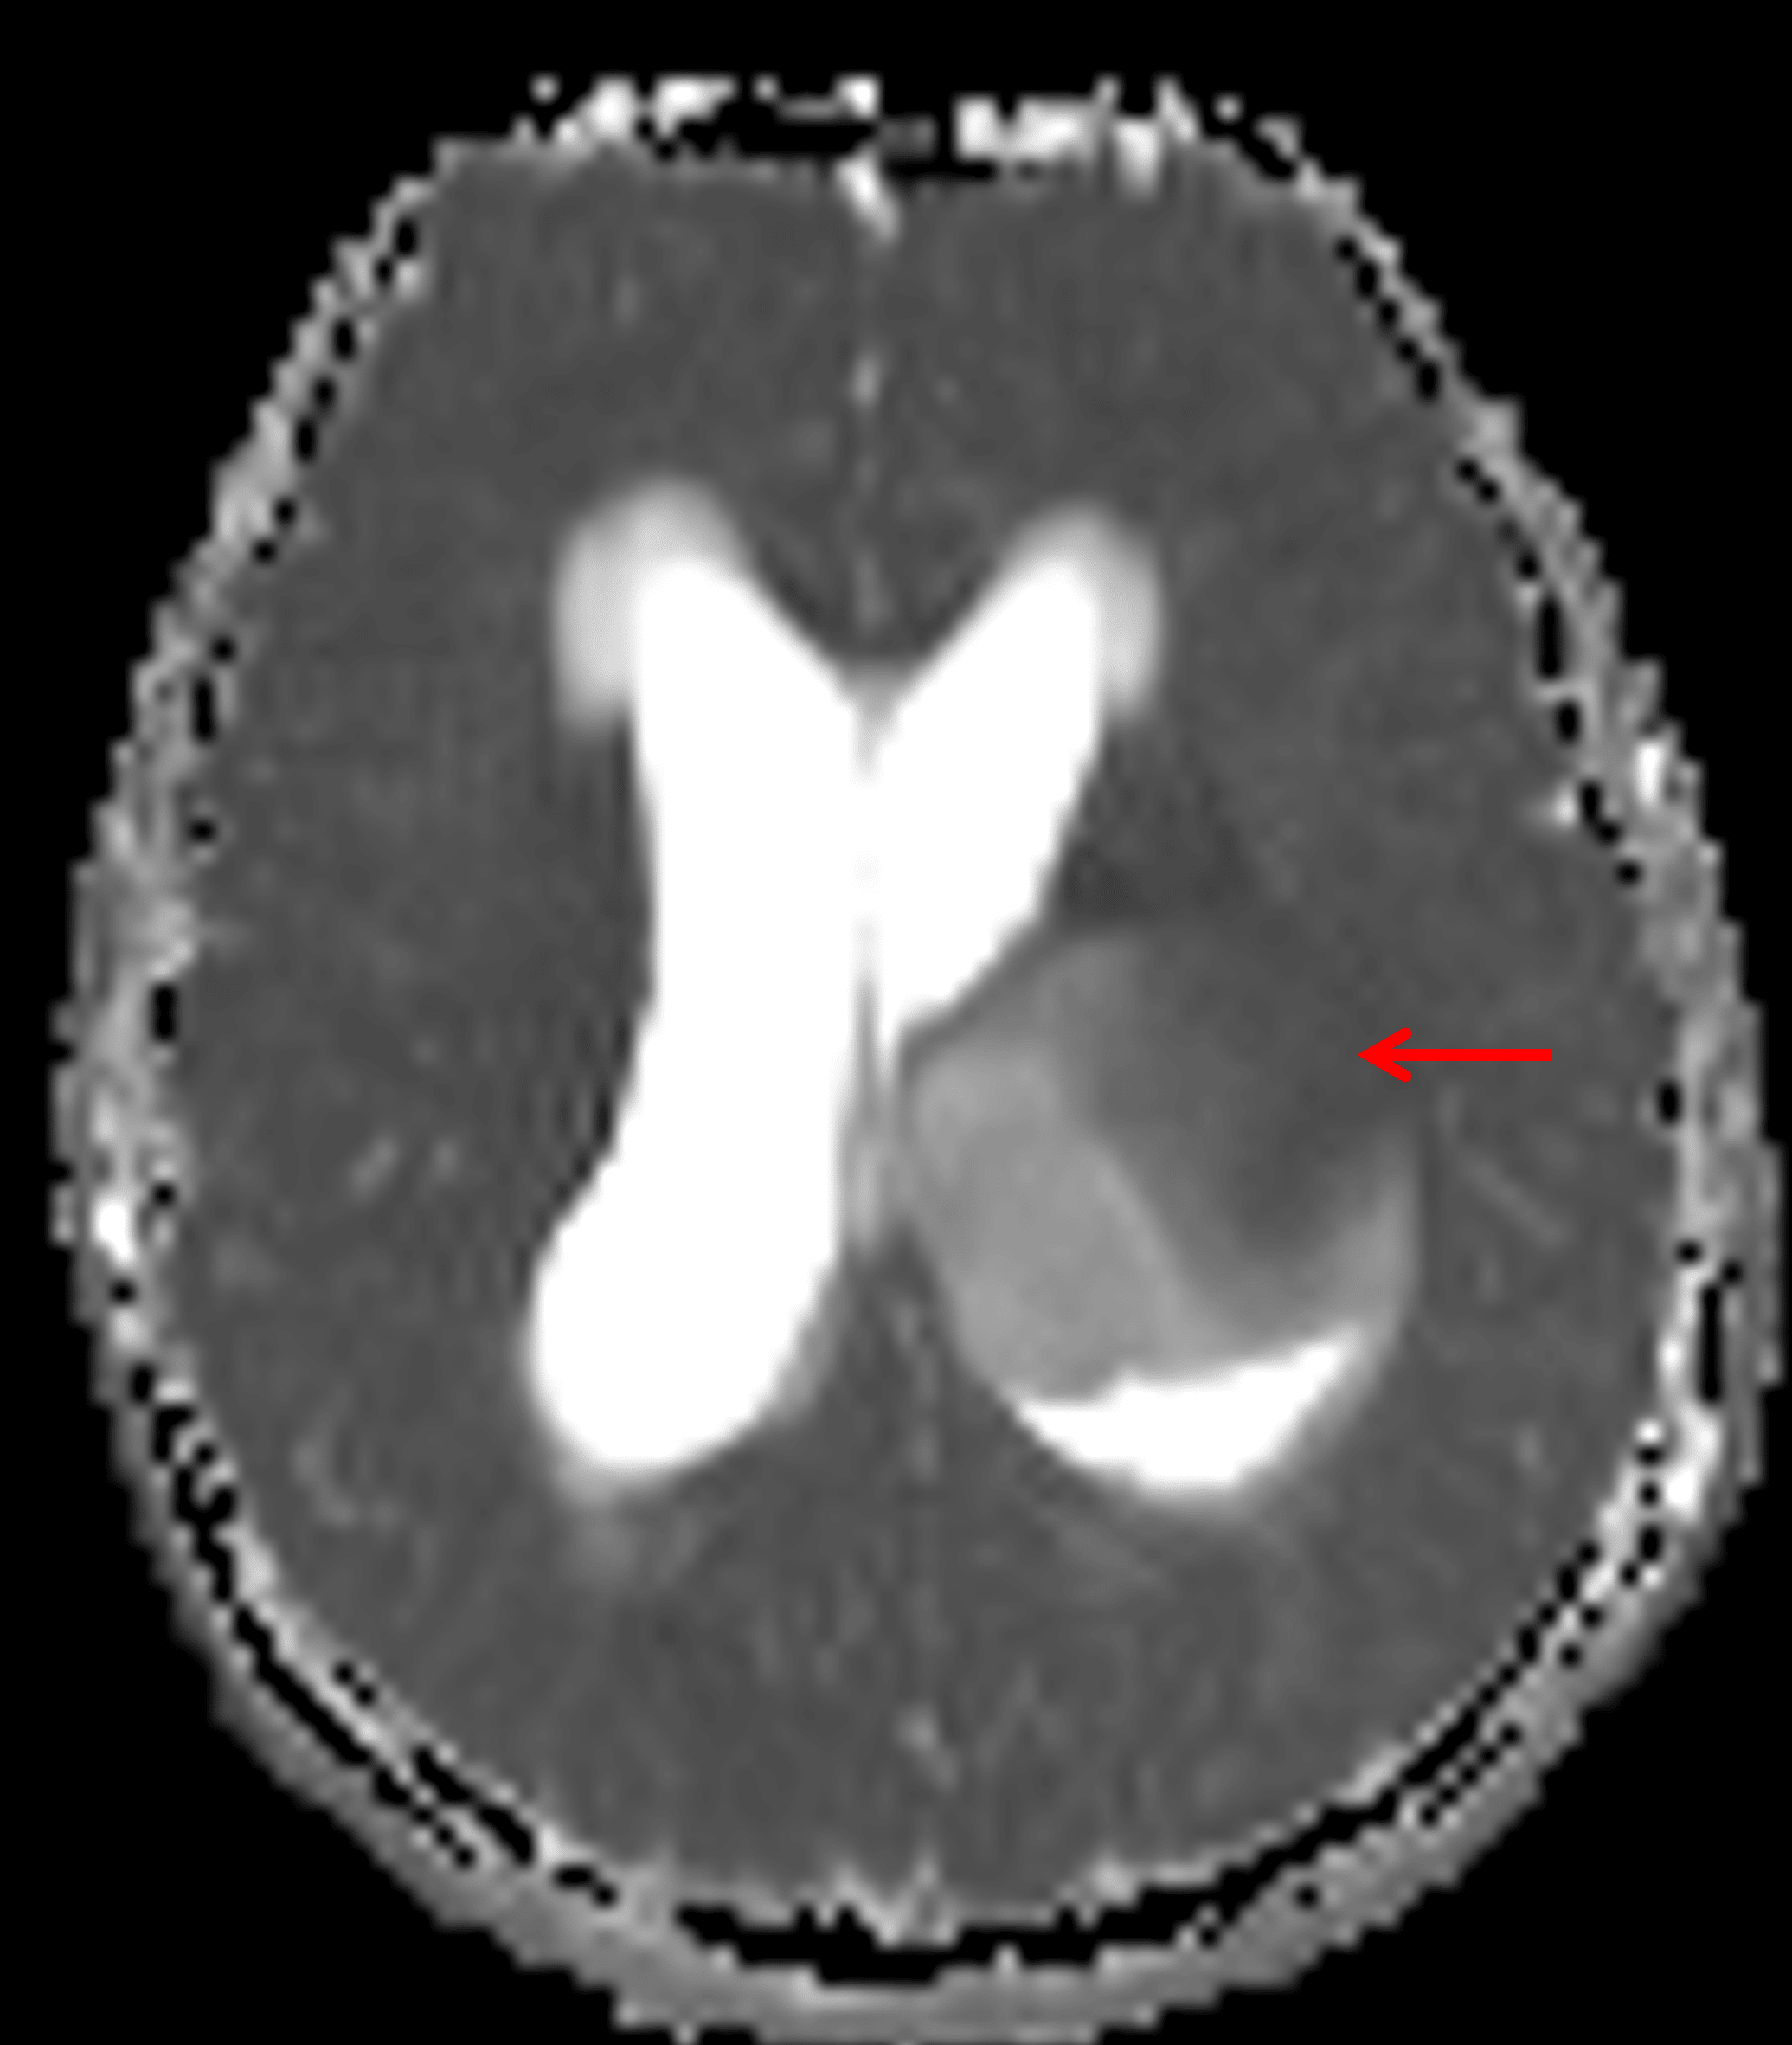

- T1 hypointense, T2/FLAIR hyperintense, nonenhancing mass measuring 4.6 x 5.5 x 5.8 cm centered in the left thalamus with inferior extension into the left eccentric midbrain, lateral extension into the posterior limb of the left internal capsule, and superior extension into the left frontoparietal periventricular white matter

Large, relatively homogeneous T2/FLAIR hyperintense mass centered in the left thalamus (red arrow), consistent with a diffuse midline glioma.